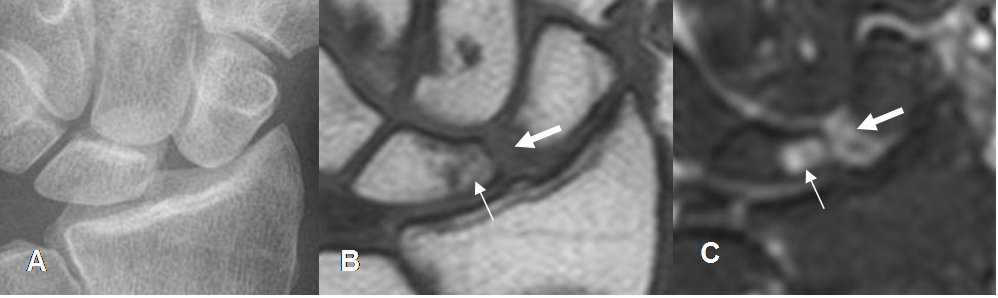

Fig 72. Ruptura del ligamento escafosemilunar y contusión osea.

A: Rx AP de muñeca. Aumento del espacio escafosemilunar.

B: RM coronal en T1 y C: RM coronal en STIR. Edema oseo del hueso semilunar (Flecha delgada) y líquido en el espacio mediocarpal. (Flecha gruesa).